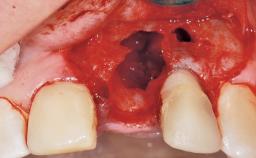

Late Placement of an Implant in a Maxillary Left Central Incisor Site

A 30-year-old female patient had lost tooth 21 and was referred to our clinic for consultation and treatment. Due to advanced apical infection, tooth 21 had been extracted two months earlier at another clinic and an acrylic-resin tooth had been bonded to the adjacent teeth. The patient desired implant treatment to avoid any damage to the adjacent natural teeth. While the patient had no history of any systemic disorder, she was a heavy smoker and exhibited medium to advanced periodontitis in the entire jaw. After the initial treatment to achieve a pocket probing depth of less than 4 mm and no bleeding on probing, a decrease in the height of the papillae mesial and distal to the extraction site and overall gingival recession were observed.

Soft Tissue Anatomy Intact Defective

Bone Volume Horizontally and vertically sufficient Horizontally deficient Deficient vertically or deficient vertically AND horizontally

Bone Volume Deficient horizontally, requiring prior grafting